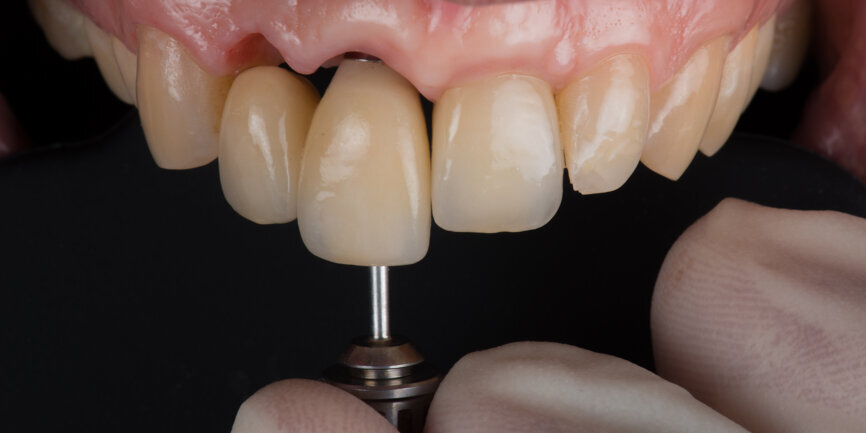

A Regular Base (RB) titanium temporary abutment for a crown was placed and a laboratory-made shell was positioned without interference with the temporary abutment (Fig. 9). The surgical site was protected with a small piece of rubber dam (Fig. 10), and the abutment was connected to the shell with a dual-curing luting composite (Fig. 11). The development of a proper emergence profile will be done extra-orally (Fig. 12) to produce the screw-retained temporary crown.

Two months after the extraction of tooth #12, an implant level impression was taken for final restoration using a digital scan body (Fig. 18) and a digital intra-oral scanner (TRIOS, 3Shape). A zirconia cantilevered fixed implant-supported bridge was fabricated according to a fully digital workflow (Figs. 19 & 20). The screw-retained bridge was then torqued to 35 N cm (Figs. 21 & 22). The follow-up, ten months after implant placement, showed a well-preserved gingival contour (Figs. 23 & 24).